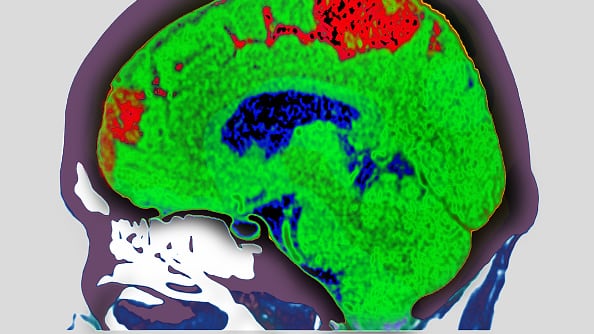

Um acidente vascular cerebral é designado como qualquer anormalidade no cérebro resultante de um processo patológico dos vasos sanguíneos. Ou seja, obstrução por trombos ou êmbolos, ruptura do vaso e lesão ou distúrbio da permeabilidade da parede vascular.

Se o cérebro não recebe sangue suficiente para fornecer o oxigênio e os nutrientes de que precisa, as células cerebrais serão danificadas ou morrerão, resultando em um AVC isquêmico ou Infarto Cerebral Isquêmico.

Uma das causas deste incidente médico é quando um coágulo sanguíneo obstrui uma artéria no cérebro (AVC isquêmico). Os sintomas do acidente vascular cerebral geralmente surgem repentinamente, em questão de segundos ou minutos.

Num quadro crítico, o médico pode recomendar a realização de uma cirurgia. Isso dependerá do tipo de acidente que a pessoa sofreu, não sendo recomendado para todos.